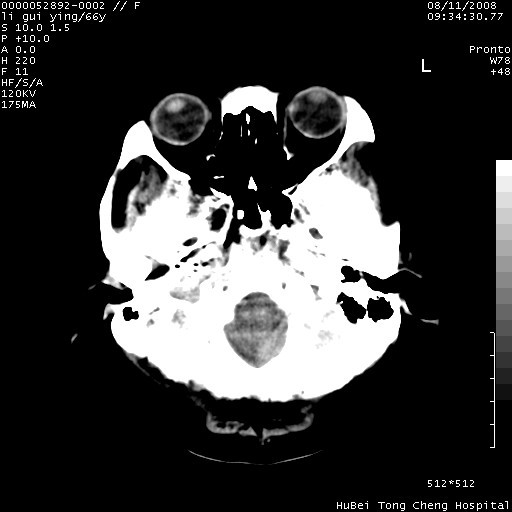

以下是引用yangyudong333在2008-8-12 12:22:00的发言:[br]1.病灶呈圆形[br]2.周围无水肿带[br]3.密度不均匀,内有点状钙化[br]4.无占位效应[br] 考虑良性占位性病变,血管瘤可能性大